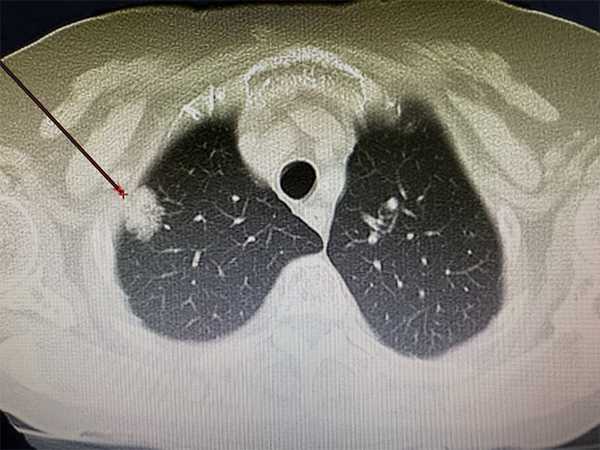

治疗后的CT改变

术前,胸外科组织影像科、麻醉科、急诊科等多科室开展MDT会诊,制定了多个应急预案,为手术做好万全准备。手术当天,胸外科团队为张奶奶实施了局部麻醉下冷冻消融手术,仅用时2小时,就完成了冷冻消融及组织活检。张奶奶说:“这么大的手术我都没什么感觉。”术后第二天复查双肺CT,达到预期效果,张奶奶当日便出院。